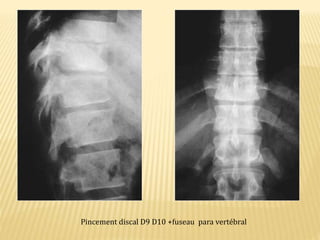

Pincement discal D9 D10 +fuseau para vertébral

Pincement discal D9D10 +fuseau para vertébral